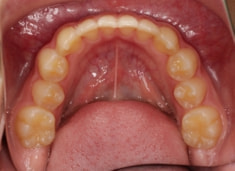

治療前

治療開始時

上下顎のギャップはありますが、顔面自体の幅径は良好な値を示していますので、スペース不足は拡大することによって解決できポテンシャルはあると考えられます。